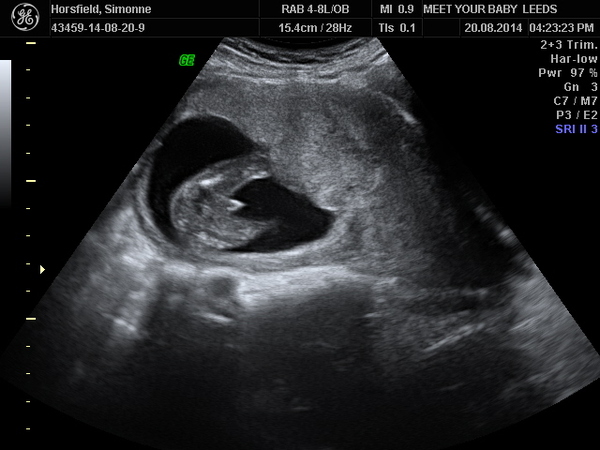

SimmyCZ · 23/08/2014 10:20

I had a private gender scan on wednesday. I was 16 weeks and 3 days. This is my 5th pregnancy 3rd baby. I have 2 boys and just been told im having another boy. i have attached a picture of scan can anyone tell me if this is defo a boy.